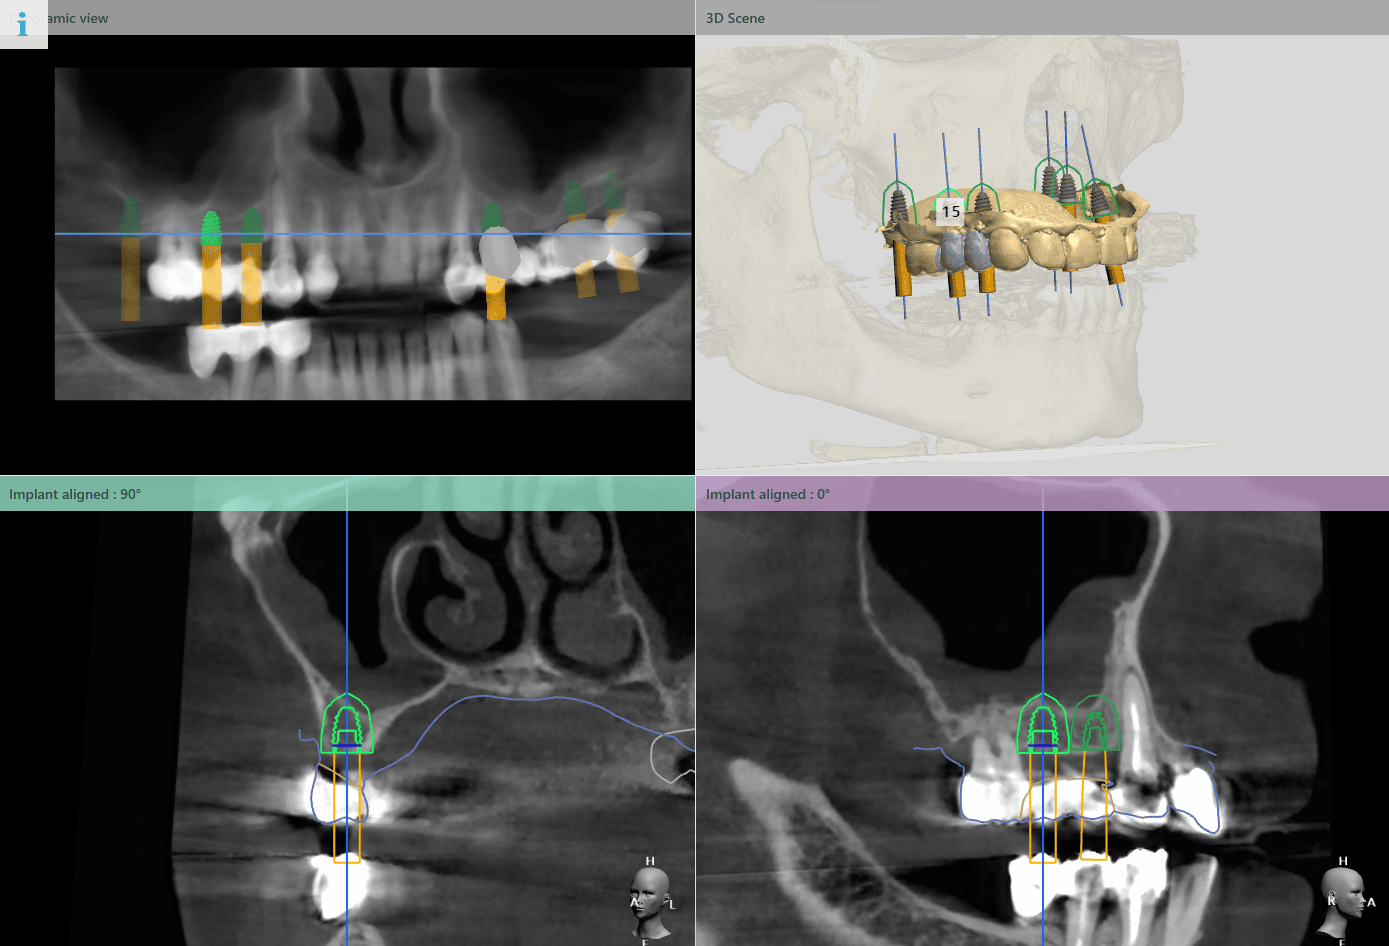

În urma evaluării CBCT-ului s-a constatat necesitatea realizării augmentarii osoase ăn zona posterioară maxilară, lifting sinusal maxilar bilateral odată cu inserarea implanturilor.

Pentru a se asigura că implanturile dentare vor fi plasate în poziția ideală din punct de vedere estetic și funcțional, medical implantolog a recomandat inserarea implanturilor dentare cu ajutorul ghidului chirurgical.

Medicul specialist a efactuat scanarea digitală a arcadelor pe care a trimis-o tehnicianului dentar DigiRay, împreună cu CBCT-ul pacientului.

Odată planficată și agreată poziția și axul de inserție al fiecarui implant, tehnicianul DigiRay efectuează designul șablonului chirurgical și printarea acestuia dintr-o rășină bio-compatibilă.